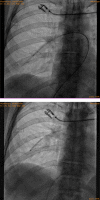

Contraceptive implant migration into the pulmonary circulation is an uncommon, but potentially serious complication. We describe an "aspiration" technique for percutaneous retrieval of a contraceptive implant from a subsegmental pulmonary artery, using a Penumbra Neuron MAX 088 guiding catheter and a Merit Medical VacLok Vacuum Pressure Syringe, as an alternative to the previously described snare technique. Our patient had an uneventful recovery and was discharged home on the same day.